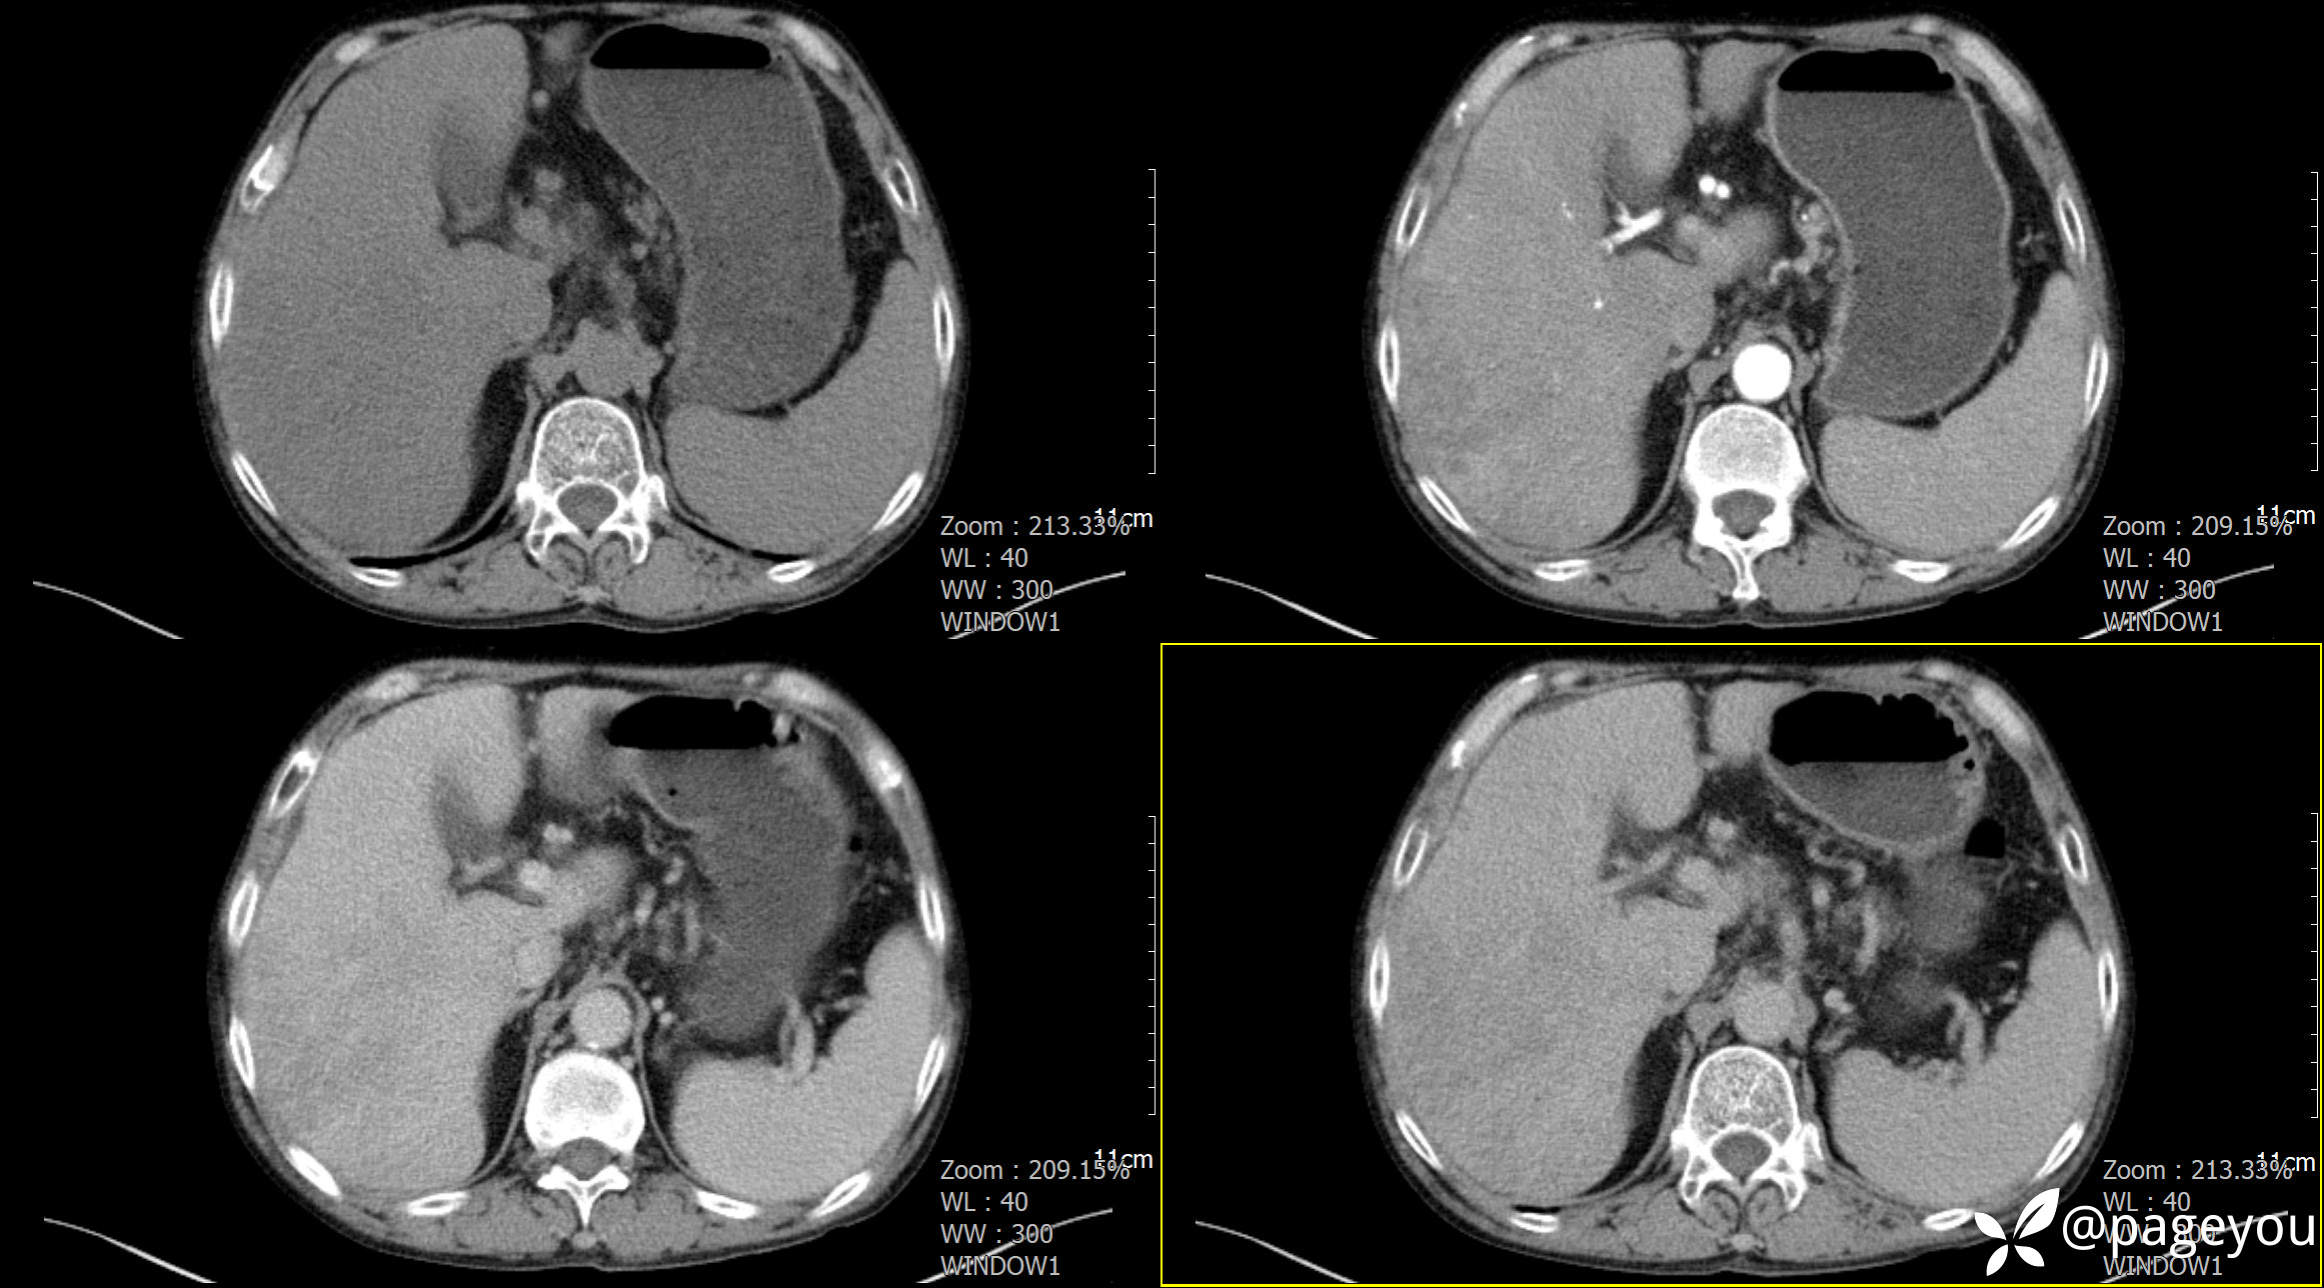

CT检查: